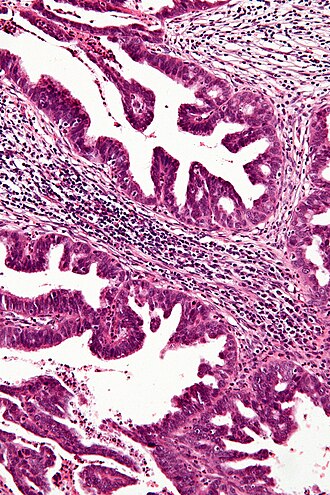

Cervical adenocarcinoma. H&E stain. | |

Microscopic

Features:

- Cells with moderate cytoplasm, typically with basally stratfied nuclei.

- Cytologic changes:

- Nuclear hyperchromasia.

- Nuclear pseudostratification.

- Nuclear enlargement.

- Stromal changes - "desmoplastic stroma/desmoplastic reaction".

- Fibrosis/streaming cells.

- Abnormal architecture:

- Gland fusion.

- Glands too deep -- very fuzzy criterion.